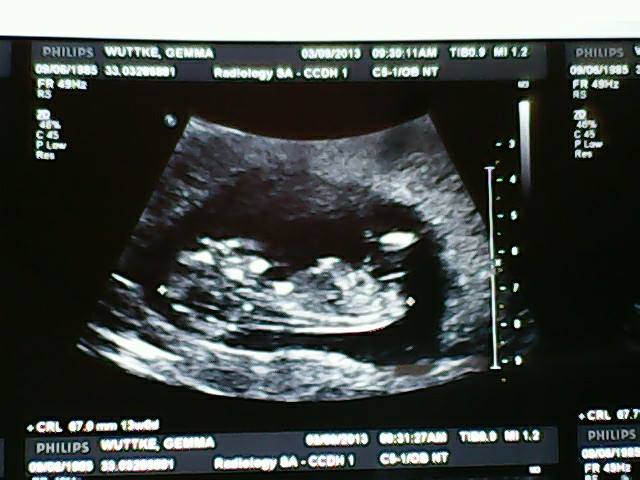

Attachment 14023Attachment 14024

Its called Ultrasound Prediction